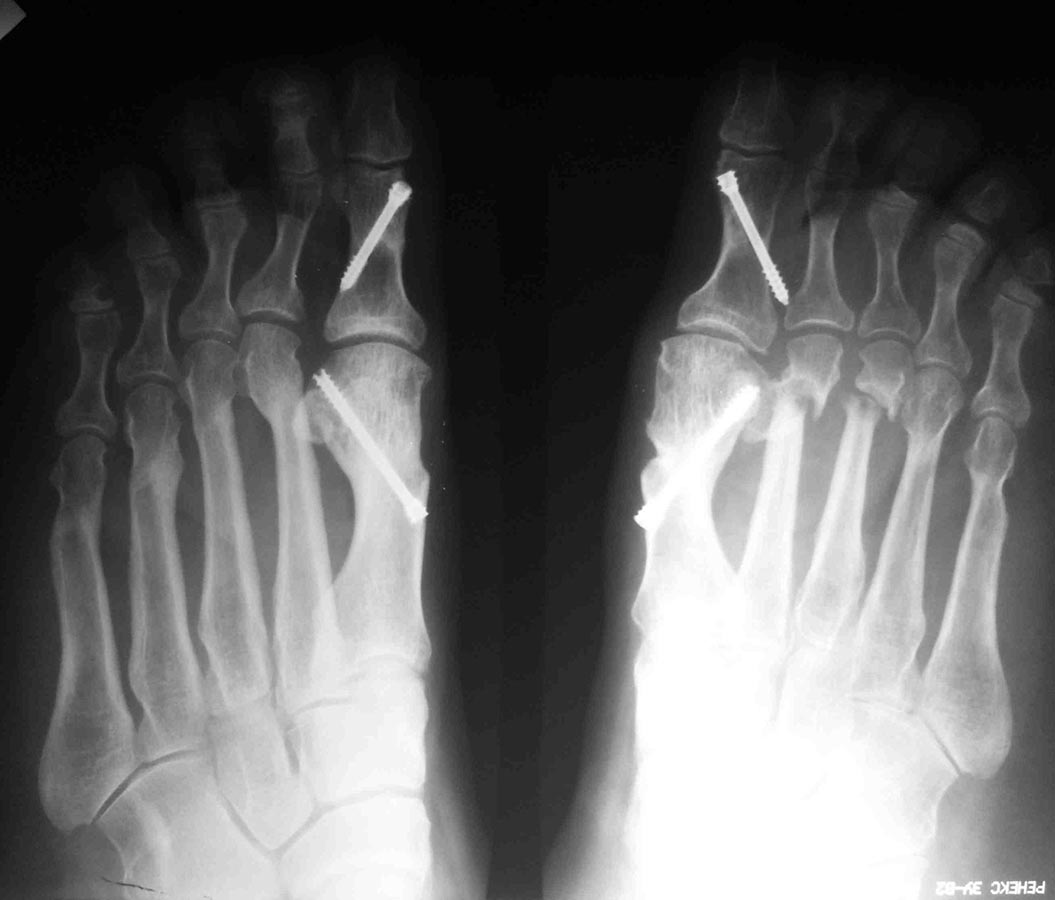

Уважаемые коллеги, я понимаю, что уже утомил вас оперированными стопами,

но помогите еще с одним случаем

Женщина около 50, активная, оперирована 1 год назад. Тип остеотомии в

выписке не указан (похоже с 1-го по 5-ую + фаланги). Сожалею. что фото

стопы не удалось выложить, клинически - выраженная девиация всех пальцев

стопы слева. Что предпринять? Латеральный релиз, утягивание (лучшего

синонима не нашел) медиальной капсулы+остеотомии 4-5 с нормальной

повязкой? 1-ый луч - SERI (для жесткости остальных- к нему притянуть),

но, головка и так скомпрометирована (или это не брать в расчет?)+

освежение ложняков+ коррегирующая остеотомия 4-5 Weil с фиксацией винтом

(или без фиксации?). С фалангами что делать? Кажется,

что ничего?